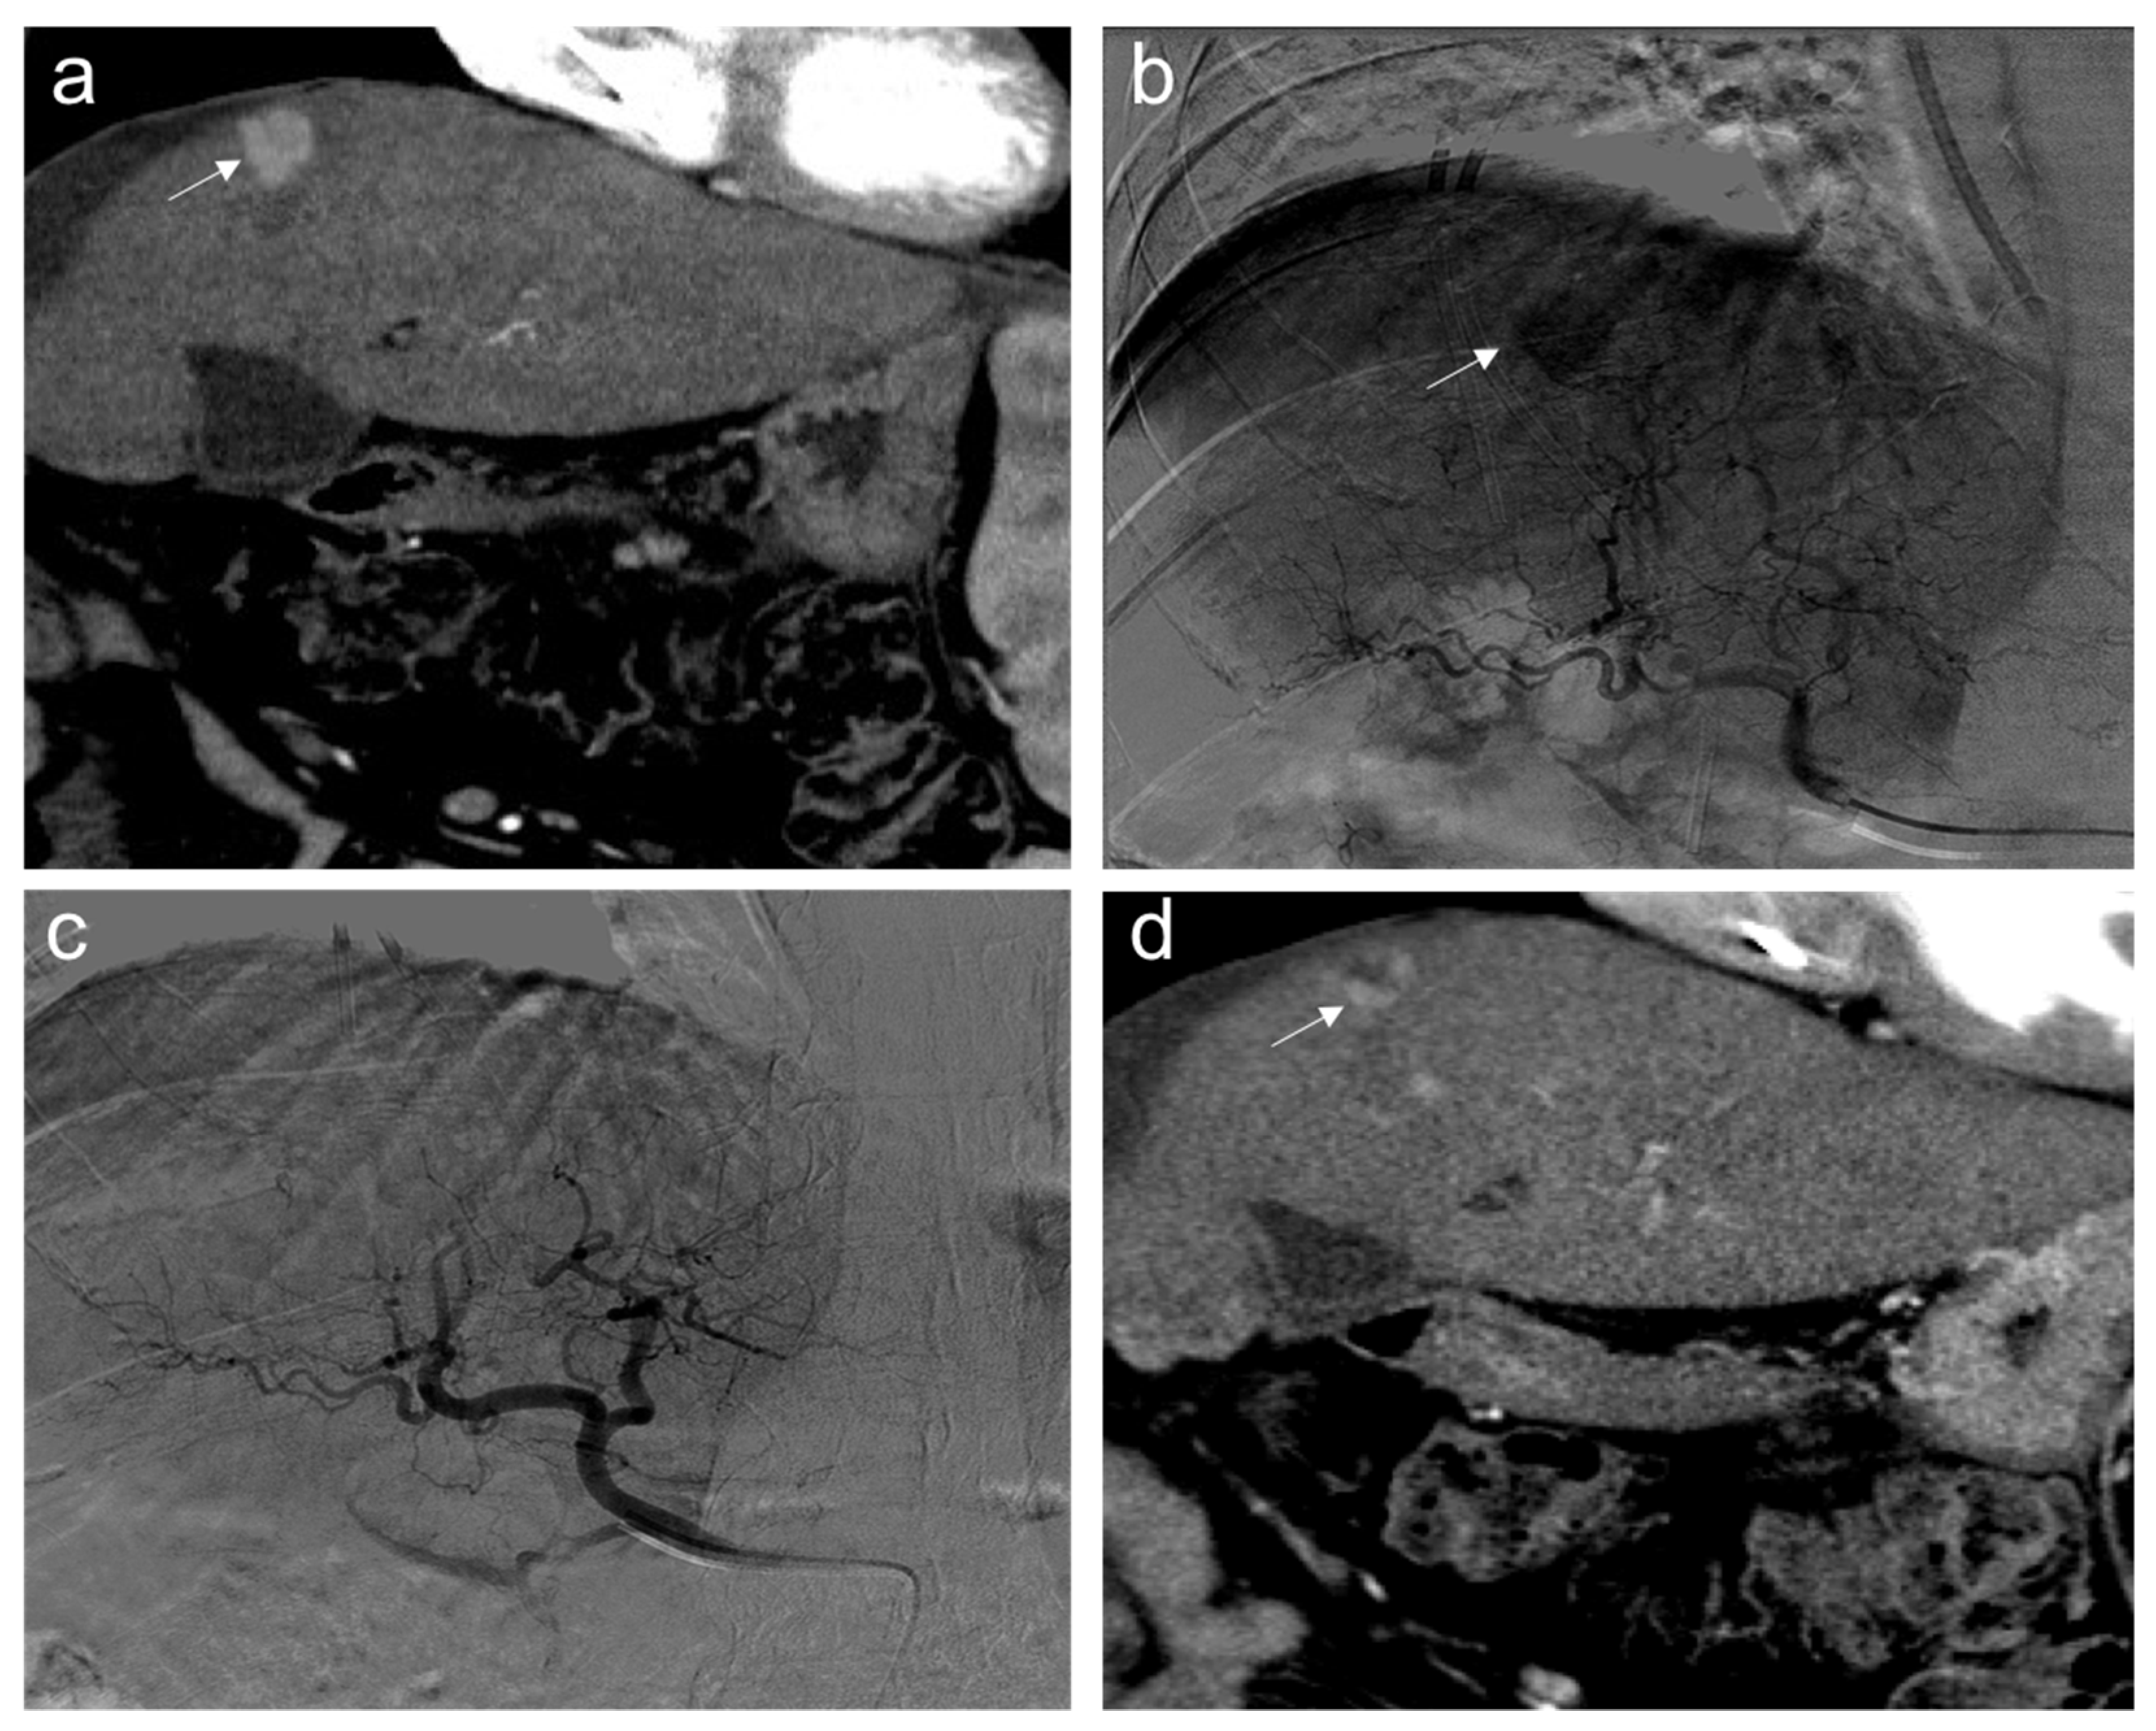

2. TACE Technique

3. Treatment Response Criteria